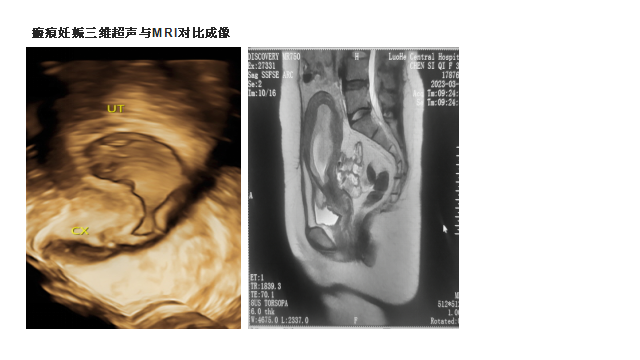

4、判断早孕期孕囊着床部位:尤其对宫角妊娠、间质部妊娠以及瘢痕妊娠等有较好的诊断价值,其准确性远超普通二维阴超。